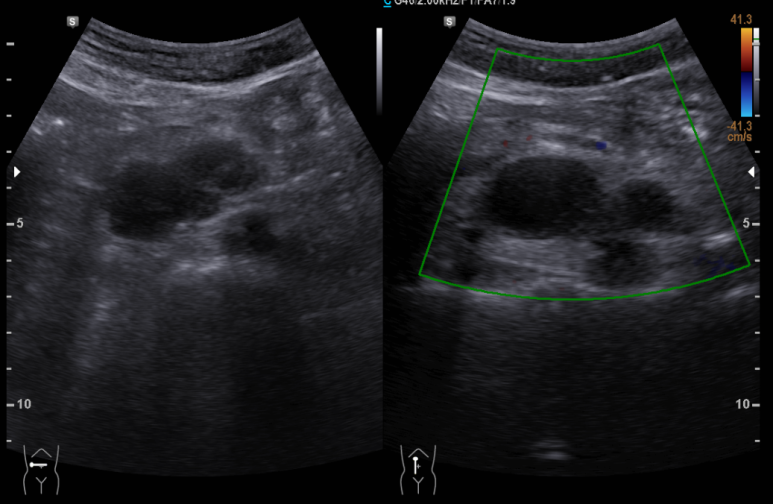

5.6 cm 낭성 종양 직 상부로 상장간막 동맥, 정맥이 위치하고 있다. (파란 별 아래 위치)

진단; Cystic mass

ddx; lymphangioma, cystic change of neurogenic tumor, cystic lymphadenopathy

대학병원에서 CT시행 판독

; r/o lymphangioma, neurogenic tumor with cystic change, mucinous cystadenoma